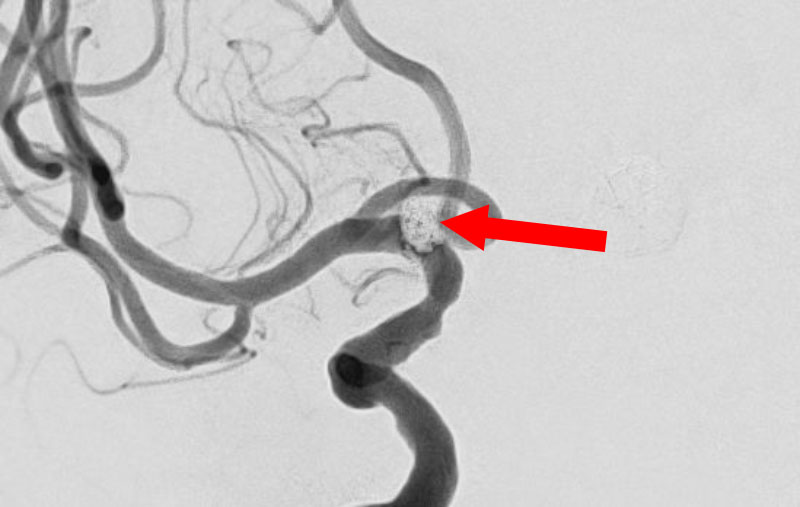

くも膜下出血

左中大脳動脈瘤破裂

40代

救急外来

No.1596 手術後